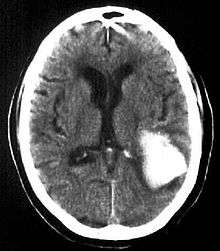

Intraparenchymal hemorrhage (IPH) is one form of intracerebral bleeding in which there is bleeding within brain parenchyma. The other form is intraventricular hemorrhage (IVH).

Computed tomography (CT scan): A CT scan may be normal if it is done soon after the onset of symptoms. A CT scan is the best test to look for bleeding in or around your brain. In some hospitals, a perfusion CT scan may be done to see where the blood is flowing and not flowing in your brain.

Intracerebral hemorrhages is a severe condition requiring prompt medical attention. Treatment goals include lifesaving interventions, supportive measures, and control of symptoms. Treatment depends on the location, extent, and cause of the bleeding. Often, treatment can reverse the damage that has been done.